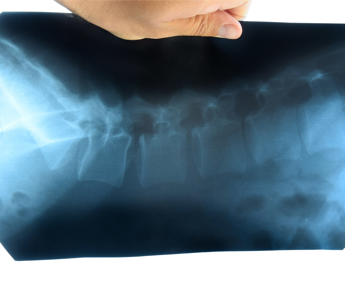

(Adnkronos) – I pazienti affetti da spondilite anchilosante, nota anche come spondiloartrite assiale radiografica (r-axSpA), trattati con bimekizumab, un inibitore di IL-17A e IL-17F, hanno mostrato miglioramenti sostenuti in termini di segni, sintomi, attività di malattia, funzionalità fisica e qualità della vita correlata alla salute, fino a 5 anni, con un profilo di sicurezza costante per tutto il periodo di trattamento. Sono i dati a lungo termine dello studio Be-Agile di Fase 2b su bimekizumab e della sua estensione in aperto (Ole) diffusi da Ucb, azienda biofarmaceutica in occasione dell’American College of Rheumatology (Acr) Convergence 2023, svoltosi recentemente a San Diego. La spondiloartrite assiale (axSpA) – riferisce una nota – è una malattia infiammatoria cronica, immuno-mediata che colpisce principalmente la colonna vertebrale e le articolazioni che collegano il bacino e la colonna vertebrale inferiore (articolazioni sacroiliache). Il sintomo principale, nella maggior parte dei pazienti, è il dolore infiammatorio alla schiena, che migliora con l'esercizio fisico, ma non con il riposo. Altre caratteristiche cliniche comuni includono spesso uveite anteriore, entesite, artrite periferica, psoriasi, malattia infiammatoria intestinale e dattilite. L'esordio dell'axSpA avviene solitamente prima dei 45 anni. "Le persone affette da spondilite anchilosante – afferma Emmanuel Caeymaex, Executive Vice President, Immunology Solutions and Head of U.S. di Ucb – in molti casi non raggiungono un controllo a lungo termine della malattia, hanno” quindi “necessità di ulteriori opzioni terapeutiche. I dati a 5 anni di bimekizumab hanno dimostrato miglioramenti sostenuti in diversi ambiti della malattia e un profilo di sicurezza coerente con le osservazioni precedenti". "Questo – spiega Atul Deodhar, professore di Medicina, Oregon Health & Science University, Divisione di Artrite e Malattie Reumatiche di Portland – è il primo rapporto sulle risposte Asas40 – una risposta di miglioramento del 40% secondo i criteri dell'Assessment of Spondyloarthritis International Society – a 5 anni, in pazienti con spondilite anchilosante, ad avere utilizzato un'analisi conservativa di imputazione dei non-responder. Utilizzando questo metodo, i dati hanno dimostrato che almeno la metà dei pazienti trattati con bimekizumab ha ottenuto miglioramenti duraturi nel corso dei 5 anni di trattamento". Nell'Unione Europea bimekizumab è approvato per il trattamento della psoriasi a placche da moderata a grave negli adulti candidati alla terapia sistemica, per il trattamento dell'artrite psoriasica attiva, da solo o in combinazione con metotrexato, negli adulti che hanno avuto una risposta inadeguata o che sono stati intolleranti a uno o più farmaci antireumatici modificanti la malattia. Un’altra indicazione per bimekizumab nell’UE è il trattamento di adulti con spondiloartrite assiale attiva non radiografica, con segni oggettivi di infiammazione, come indicato dall'innalzamento della proteina C reattiva e/o dalla risonanza magnetica, che hanno risposto in modo inadeguato o sono intolleranti ai farmaci anti-infiammatori non steroidei, e per il trattamento di adulti con spondilite anchilosante attiva che hanno risposto in modo inadeguato o sono intolleranti alla terapia convenzionale. —salutewebinfo@adnkronos.com (Web Info)